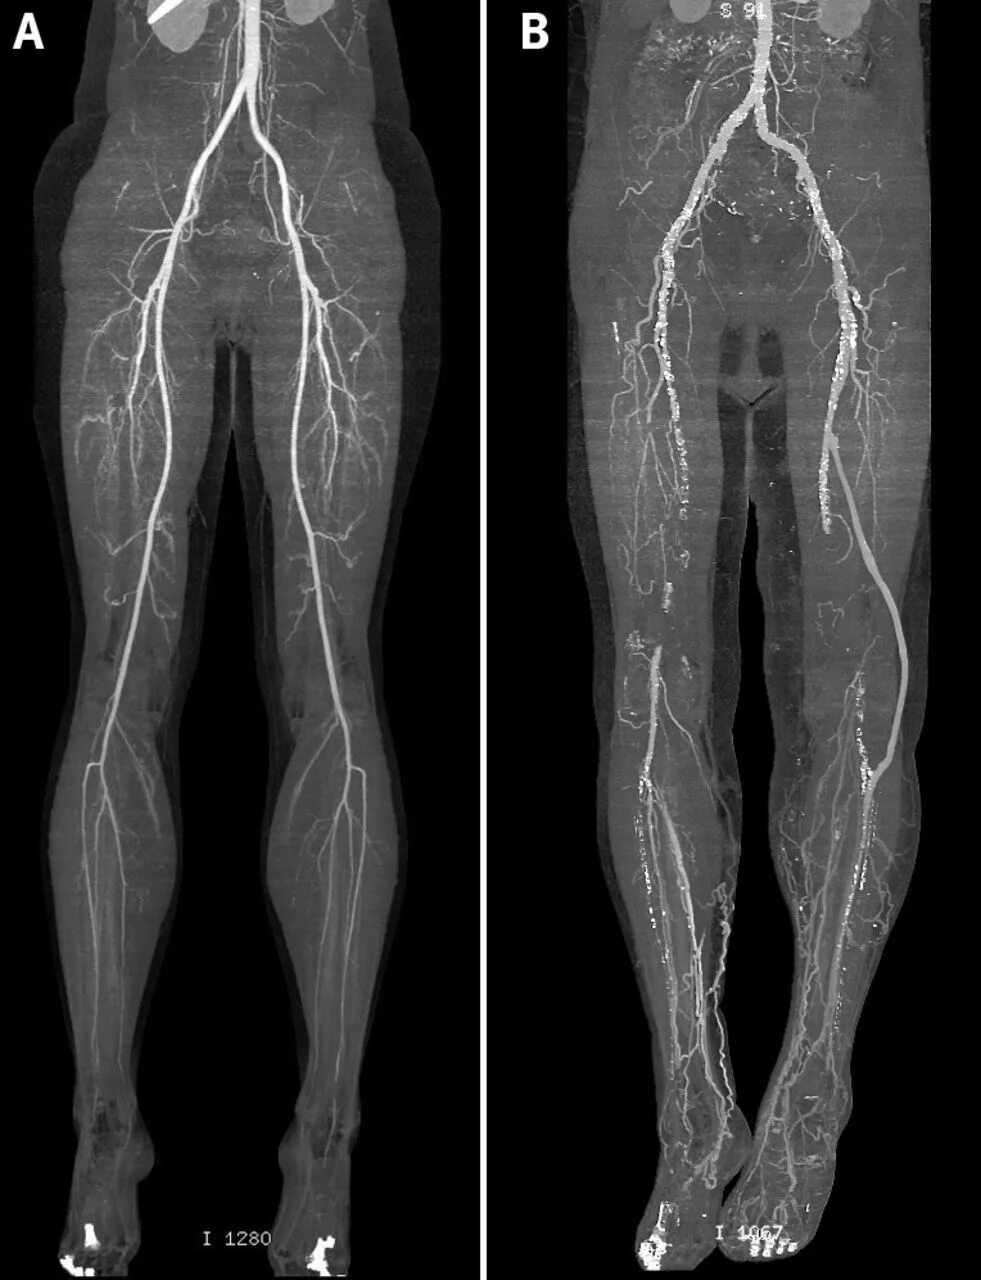

Состояние после бедренно